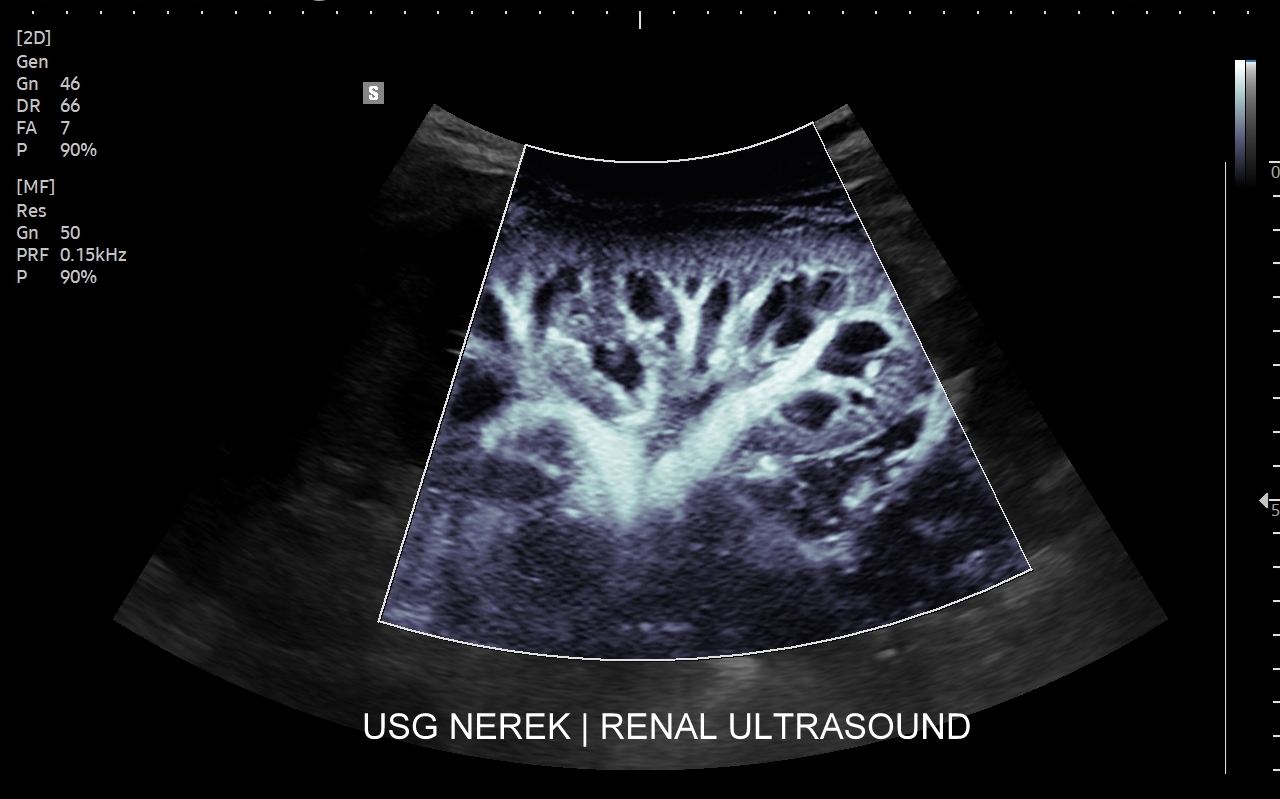

Badanie multiparametryczne MPUS jamy brzusznej

Rozwinięciem standardowego badania USG jamy brzusznej jest badanie multiparametryczne MPUS (ang. multiparametric ultrasound), w ramach którego wykorzystuje się różnorodne, nowoczesne modalności sonograficzne, takie jak tryby mikrounaczynienia MVI, B-flow, elastografię, ilościową ocenę stłuszczenia wątroby QUS, czy tryb Dopplera spektralnego, a to wszystko w celu uzyskania dodatkowej oceny funkcjonalnej i biologicznej struktur, narządów oraz tkanek jamy brzusznej. Obrazowanie MPUS niejednokrotnie poprawia także wizualną ocenę narządów wewnętrznych, czego przykładem jest zastosowanie trybu MVI w ramach bezkontrastowej angiografii sonograficznej naczyń oraz w ocenie guzów nerek. Klasycznymi i najczęstszymi zastosowaniami badania MPUS są jednakże funkcjonalna ocena wątroby w kierunku stłuszczenia, zwłóknienia, zapalenia i nadciśnienia wrotnego, a także ocena żywotności i funkcji nerek.

• Możliwość rozszerzenia zakresu badania USG w razie wystąpienia konieczności. Praktycznymi przykładami są zastosowanie trybu MVI w przypadku wykrycia guzka w nerce, czy przeprowadzenie badania elastograficznego i dopplerowskiego w wypadku stwierdzenia nieprawidłowego obrazu wątroby.